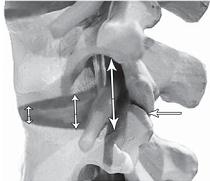

Фото № 11

На фото № 11 макета позвоночника наблюдается смещение (подвывих) суставных поверхностей дугоотростчатых суставов. Подобное смещение, как правило, происходит вследствие развития дегенеративно-дистрофических процессов в межпозвонковом диске. При этом уменьшается высота диска, сужается просвет фораминального отверстия (межпозвонкового), что может способствовать ущемлению спинномозговых корешков (нервов) и сосудов.

Фото № 12

На фото № 12 макета позвоночника наблюдается перерастяжение дугоотростчатого сустава вследствие вытяжения, расширение фораминального отверстия, а также растяжение задних отделов фиброзного кольца межпозвонкового диска и сближение вентральных (передних) отделов тел позвонков. Это приводит межпозвонковый диск в клиновидное состояние, что способствует выталкиванию содержимого межпозвонкового диска из передних его отделов в задние.